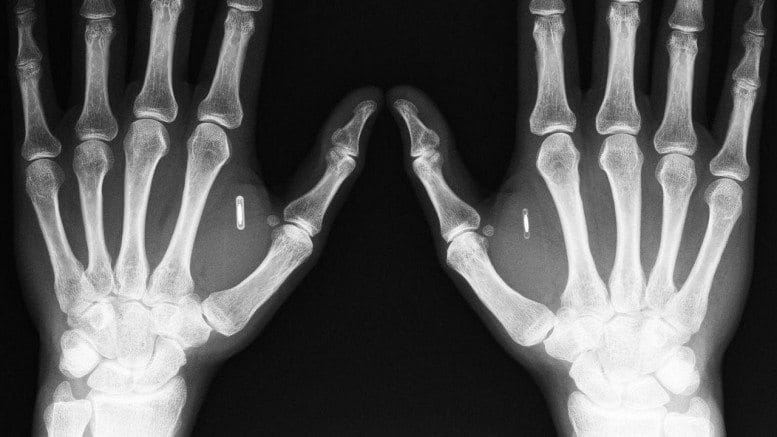

Download this post... Tim Shank can guarantee he’ll never leave home without his keys. Why? His house keys are located inside his body. Shank, the president of the Minneapolis futurist group TwinCities+, has a chip installed in his hand that can communicate electronically with his front door and tell it to unlock itself. His wife...